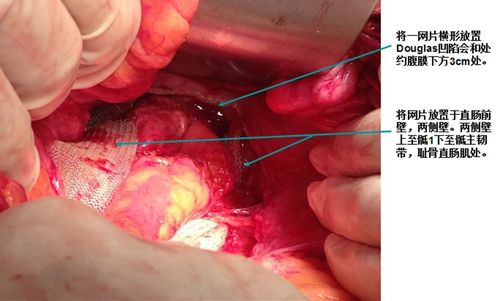

榆林一院病例分享-子宫脱垂行阴式全子宫切除术 阴道残端骶棘韧带悬吊

患者既往患有高血压病,心脏病;入院诊断:子宫脱垂3度,阴